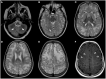

Macrocephaly affects up to 5% of the pediatric population and is defined as an abnormally large head with an occipitofrontal circumference (OFC) >2 standard deviations (SD) above the mean for a given age and sex. Taking into account that about 2-3% of the healthy population has an OFC between 2 and 3 SD, macrocephaly is considered as "clinically relevant" when OFC is above 3 SD. This implies the urgent need for a diagnostic workflow to use in the clinical setting to dissect the several causes of increased OFC, from the benign form of familial macrocephaly and the Benign enlargement of subarachnoid spaces (BESS) to many pathological conditions, including genetic disorders. Moreover, macrocephaly should be differentiated by megalencephaly (MEG), which refers exclusively to brain overgrowth, exceeding twice the SD (3SD-"clinically relevant" megalencephaly). While macrocephaly can be isolated and benign or may be the first indication of an underlying congenital, genetic, or acquired disorder, megalencephaly is most likely due to a genetic cause. Apart from the head size evaluation, a detailed family and personal history, neuroimaging, and a careful clinical evaluation are crucial to reach the correct diagnosis. In this review, we seek to underline the clinical aspects of macrocephaly and megalencephaly, emphasizing the main differential diagnosis with a major focus on common genetic disorders. We thus provide a clinico-radiological algorithm to guide pediatricians in the assessment of children with macrocephaly.